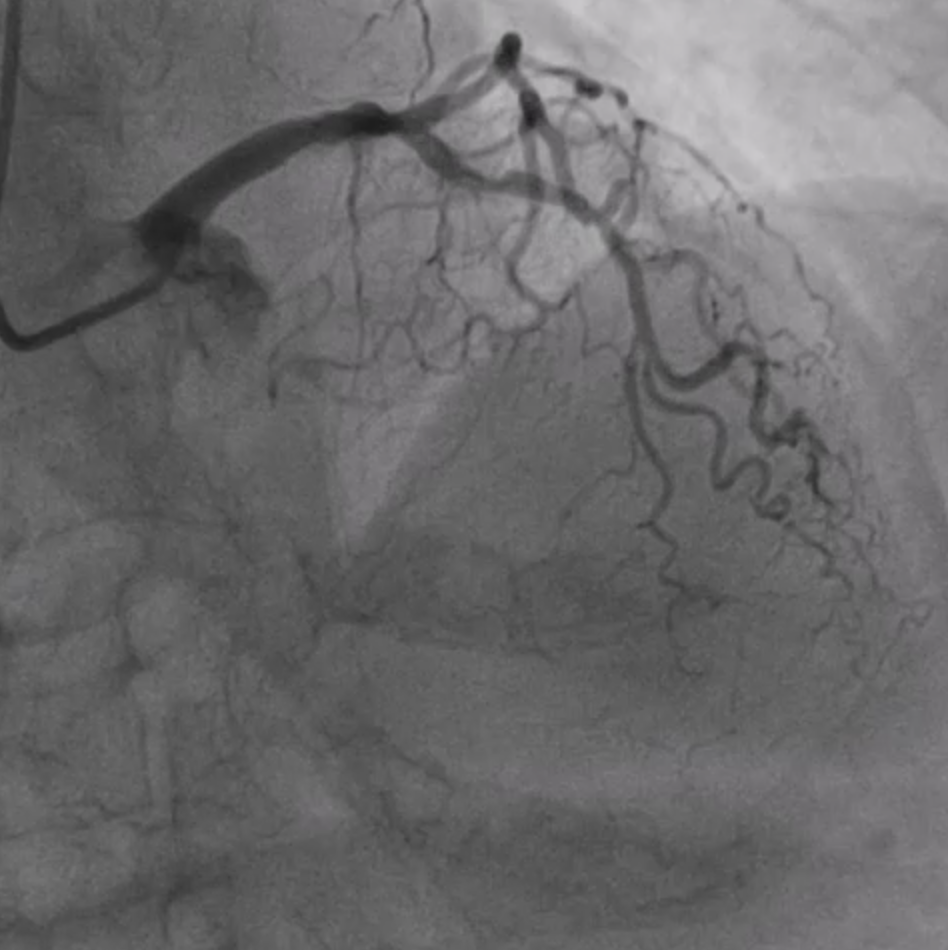

The coronary angiogram, performed via right radial access, revealed a mid-LAD chronic total occlusion (CTO), moderate stenosis in the proximal LCX, and critical stenosis in the mid-RCA. The RCA flow was TIMI 2. We decided to perform PCI on the RCA using the same access route.

We proceeded with PCI using a 6Fr JR4 guiding catheter. Mid RCA lesions were predilated with an SC 2.0. IVUS revealed severe luminal stenosis and thrombus in the mRCA, along with significant calcified stenosis in the pRCA.